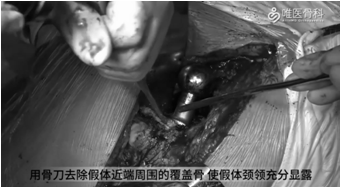

取出股骨假体:用骨刀去除假体近端周围的覆盖骨,使假体颈领充分显露,再用薄骨刀将假体与骨水泥界面进行分离。然后采用股骨假体专用工具取出假体,本病例采用音叉很容易就将假体取出。